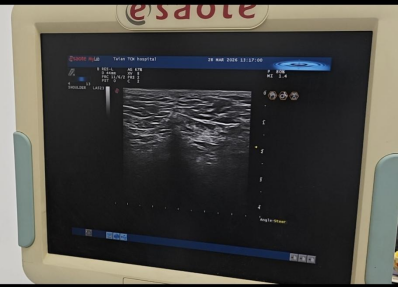

超声引导下A型肉毒毒素注射

自2025年以来,科室持续开展超声引导下A型肉毒毒素注射治疗。该技术借助超声影像实现肌肉、神经、血管等组织结构的实时可视化定位,将A型肉毒毒素注射至病变靶肌群,通过阻断神经肌肉间的冲动传导,降低肌肉过度肌张力、缓解肌肉异常痉挛或抽动。相较于传统徒手注射,超声引导下的操作定位更为精准,有助于降低周围组织损伤风险,提升治疗的安全性与有效性。该技术适用于卒中后肢体痉挛、脊髓损伤后排尿障碍、面肌痉挛、偏头痛、帕金森综合征等多种疾病引发的肌张力功能障碍。